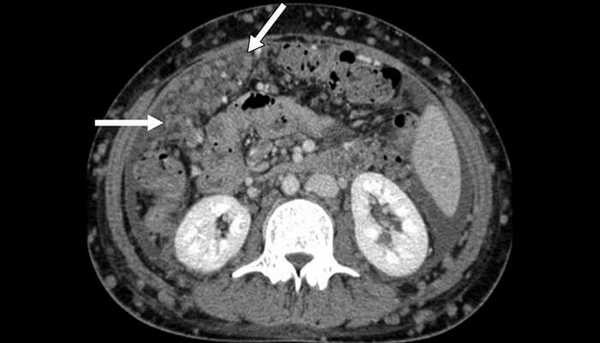

Канцероматоз брюшины, компьютерная томография

Показывает ли КТ метастазы в лимфоузлах ? Да, опухолевые очаги могут быть видны на снимках. Но их не всегда удается отличить от неизмененной нормальной ткани. Всё же для достоверного подтверждения метастатического процесса в лимфоузлах золотым стандартом является ПЭТ-КТ.

Диагностика

Компьютерная томография (КТ) не всегда позволяет дифференцировать метастазы и неизмененную ткань лимфатических узлов. Магнитно-резонансная томография (МРТ) имеет небольшое преимущество перед КТ, потому что МРТ позволяет с большей точностью определять стадию опухолевого процесса органов малого таза.